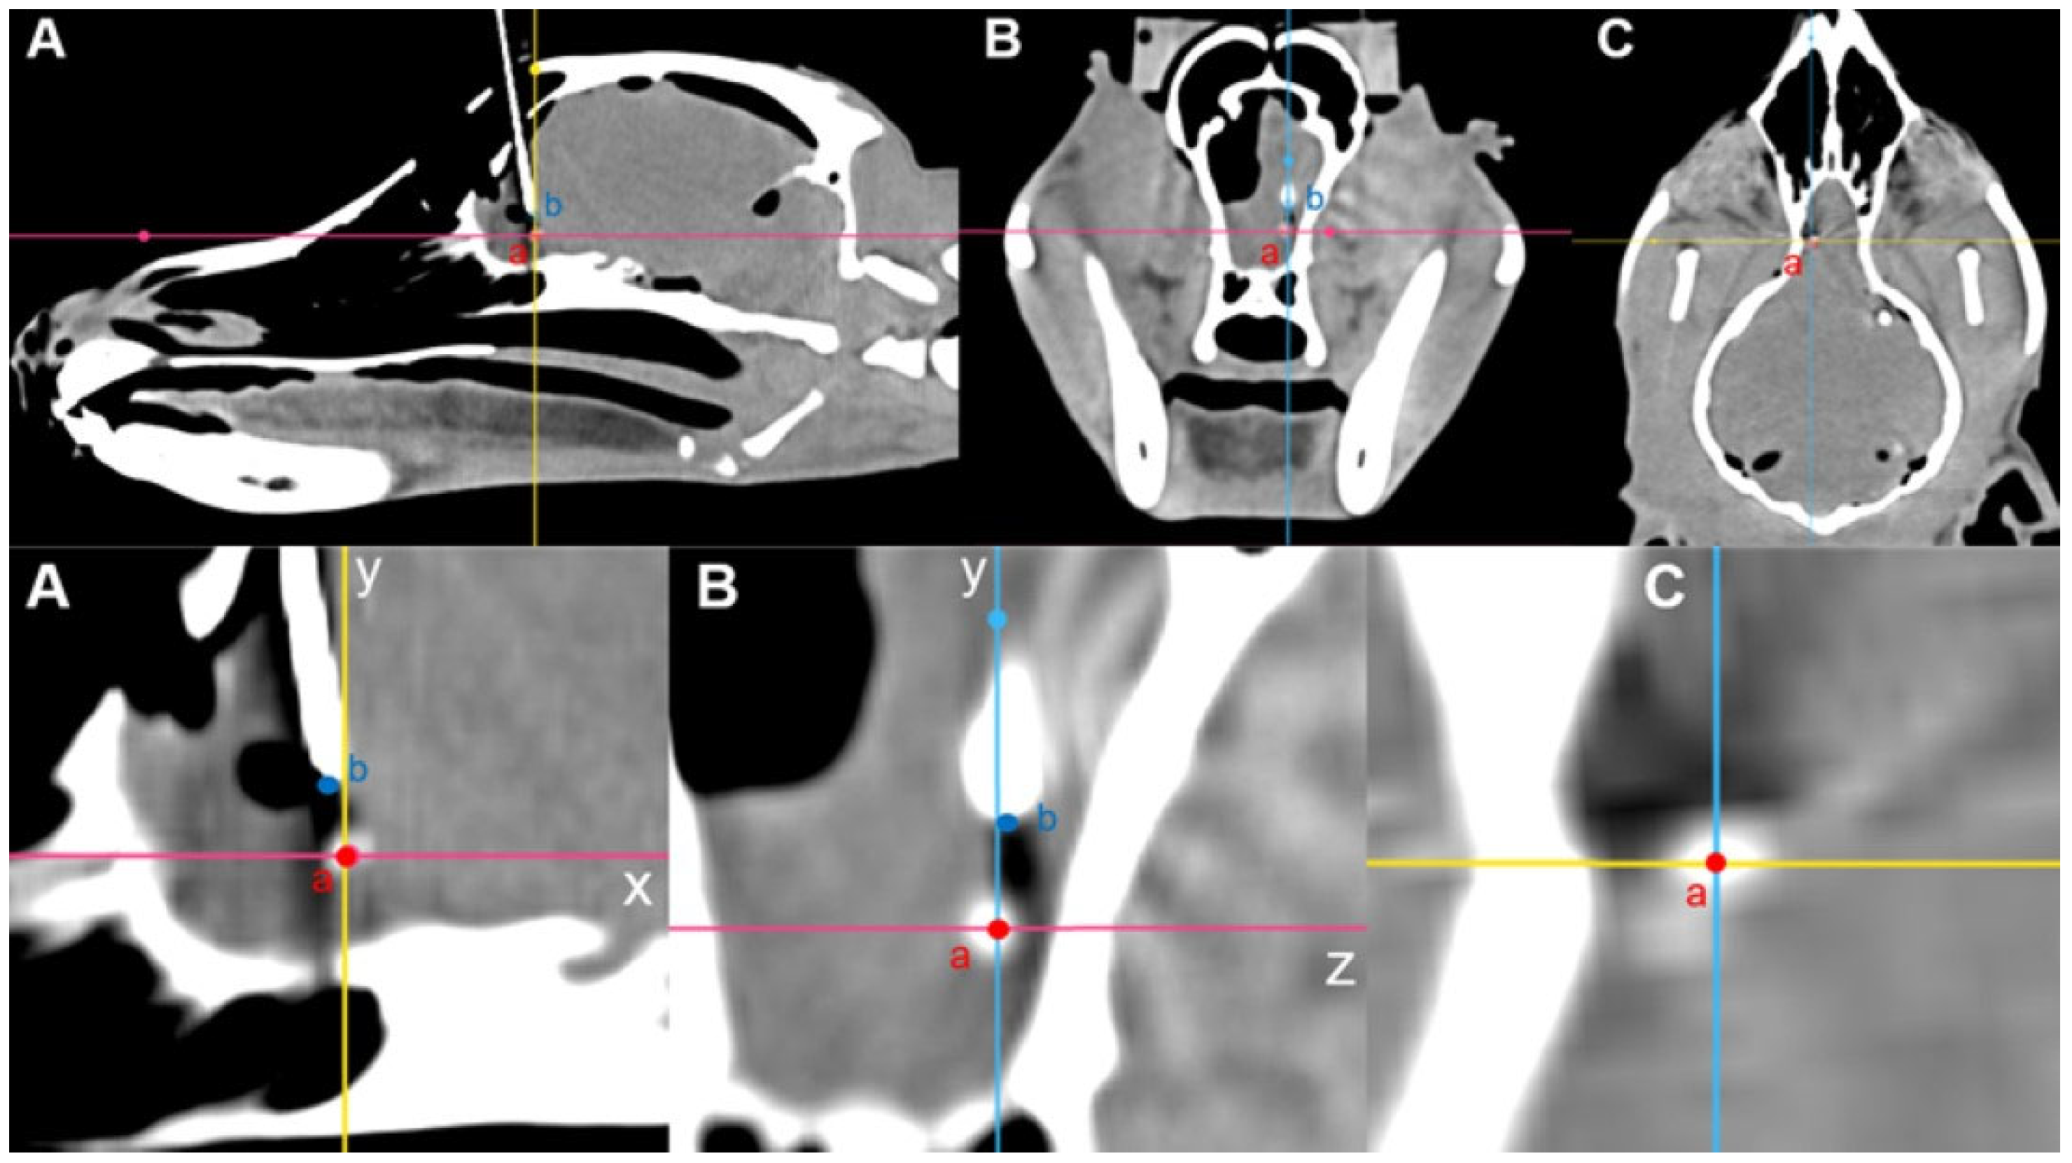

The skull was adjusted to 10% transparency and realigned along the X, Y, and Z axes. In the dorsal plane, the internasal suture to the external sagittal crest was aligned along the X-axis, while in the transverse plane, the zygomatic processes of the frontal bone on both sides were horizontally positioned. The frontal sinus, frontal lobe, and olfactory lobe were identified in the sagittal plane, and the symmetrical regions were adjusted to overlap as closely as possible along the X-Z plane. To establish the target area and for the injection of the tumor model, spherical markers with a diameter of 1.5 mm were placed in the right fronto-olfactory and left piriform lobes to visualize the ROIs (Figure 1).

2.4. Postoperative CT and 3D Volume-Rendering Analysis

Intraoperative CT images were transferred to medical image viewing software (Radiant, 22.1.1 Medixant, Poznan, Poland). The center point of the tumor model with contrast enhancement and the center point of the spinal needle tip were compared using the 3D MPR function on CT imaging. First, the axes were established based on the center of the tumor model. In the sagittal view, the horizontal line through the center was set as the X-axis, and the vertical line was set as the Y-axis. Subsequently, the changes in the X- and Y-coordinates from the center to the tip of the needle were calculated. In the transverse view, the center of the tumor model was used as the origin, with the vertical line designated as the Y-axis and the horizontal line as the Z-axis. The change in the Z-coordinate from the center to the tip of the needle was then determined. The needle placement deviation was calculated as follows: √[(△X)2 + (△Y)2 + (△Z)2] (Figure 7).

Figure 7. Calculation of needle placement error in the fronto-olfactory lobe after inserting a spinal needle, as evaluated by CT. (A) The center of the tumor model was designated as point ‘a’ and the end of the spinal needle as point ‘b’. The displacement from point ‘a’ to point ‘b’ was calculated as ΔX and ΔY. (B) The displacement from the point of origin ‘a’ to point ‘b’ was determined as ΔY and ΔZ. (C) The center of the tumor model was designated as point ‘a’.